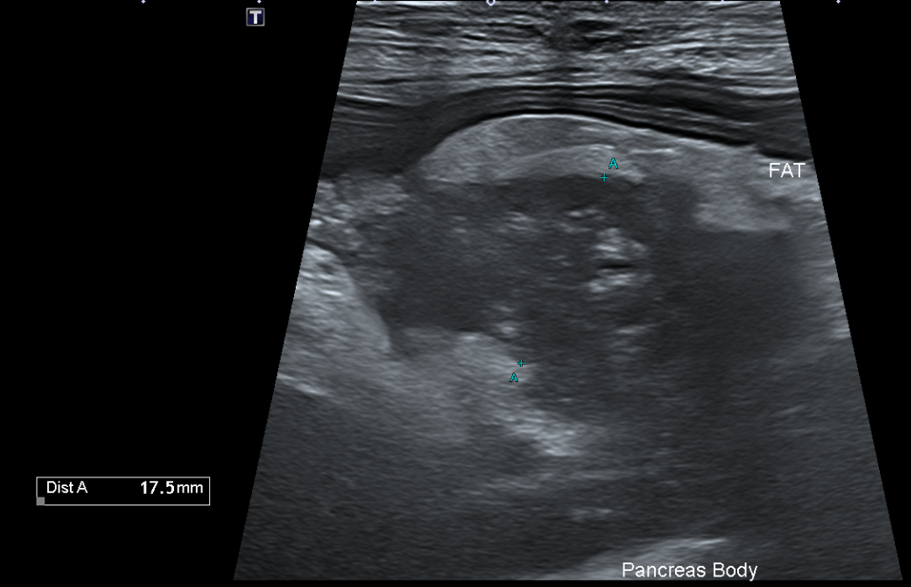

복부초음파

또한 복부 초음파상에서 뚜렷한 췌장 비후, 저에코성 음영, 주변 복막의 고에코성 소견 -> 확인되어 췌장염이 강력 의심되는 상황이었습니다.

Figure 2. 췌장 비후와 주변 복수 확인됨.

환자의 경우 뚜렷한 소화기 증상, 뚜렷한 염증 소견과 QPL 수치 상승, 복부초음파상 췌장염 비후, 복수 소견 확인되어 췌장염으로 진단되었습니다.